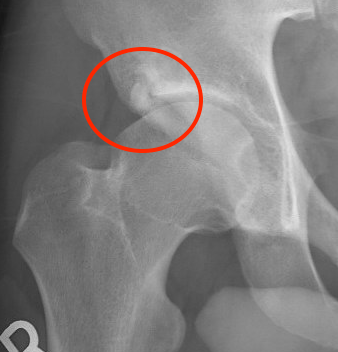

Alpha angle

Measurement

- centered in the center of the femoral head (best fit circle)

- formed by two lines

- one line center of the femoral neck axis

- a line where the femoral head leaves a best-fit circle

- higher alpha angle with Cam lesion

Barrientos et al J Hip Preserv Surg 2016

- 38 patients with Cam versus 108 control

- CT scans

- mean 48+/-5 degrees in controls

- mean 67+/-12 degrees in patients with symptomatic Cam